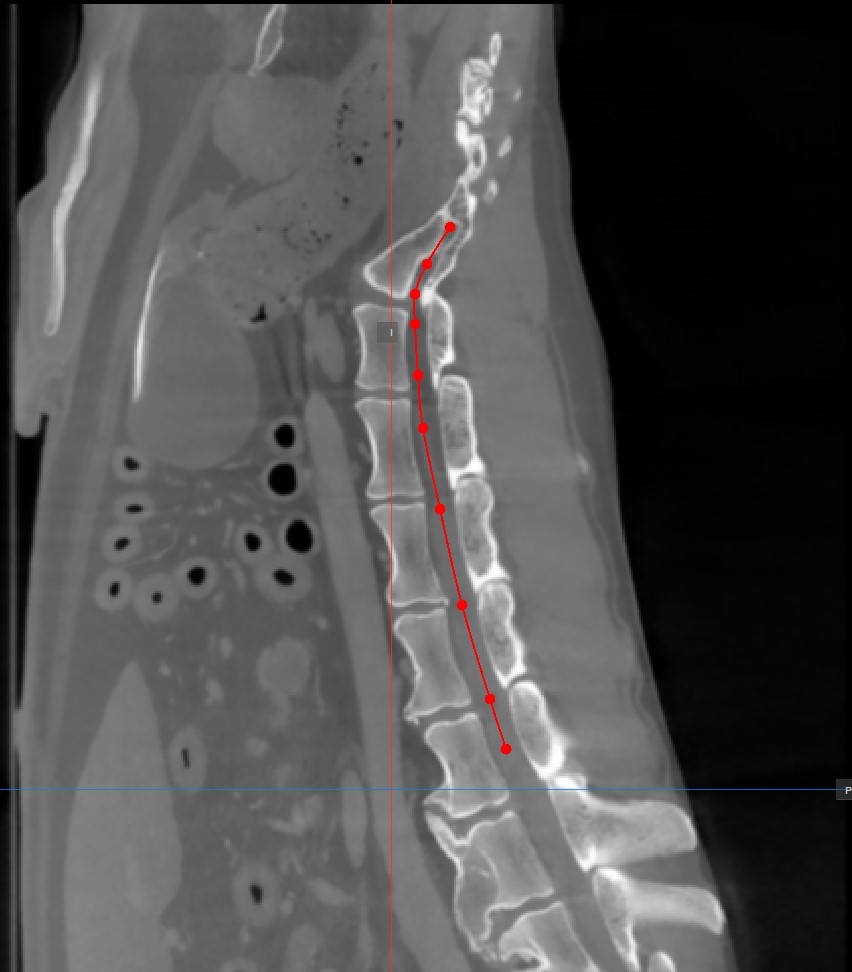

Curved MPR (CMPR) View

Curved MPR, a variation of MPR, creates cross-sectional images along a user-drawn curved path. CMPR can be especially useful when visualizing complex or irregular structures, such as blood vessels or various spinal structures.

The curved MPR straightened view, along with its associated slicers are located on the left side of the viewer, while the standard MPR in all three available planes is located on the right side of the window.

Add Curved Path Points

The Curved MPR requires a user-drawn path in order to generate the cross-sectional images. Select the Add CMPR Point tool located at the bottom section of the CMPR view to draw the required path.

• The points generating the path have to be placed on one of the three available standard MPR viewports on the right side of the window. Choose the most appropriate plane for the requirements.

• At least two points have to be placed on the images in order to generate the path. The CMPR view will be more detailed when more points are used to draw the path.

• To complete the path, toggle the Add CMPR Point tool again, or double-click with the mouse on the image after placing the last point of the path. The path will be marked in green once it’s finalized.

Hovering over the straightened view of the CMPR path will display an orange dot on the path drawn on the MPR images, highlighting the precise location of the cursor.